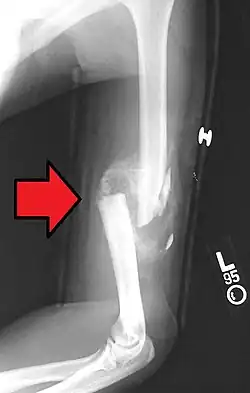

Fraturas

Nos locais de fratura óssea ocorre hemorragia, pela lesão dos vasos sanguíneos, destruição da matriz e morte de células ósseas.

Macrófagos removem o coágulo sanguíneo, restos de células e restos da matriz para que se possa começar o reparo da fratura. O periósteo e o endósteo próximos à área de fratura respondem com uma intensa proliferação, formando um tecido muito rico em células osteoprogenitoras que constitui um colar em torno da fratura e penetra entre as extremidades ósseas rompidas. Esse processo se desenvolve de modo a aparecer um calo ósseo após algum tempo.

As trações e pressões exercidas sobre o osso durante a reparação da fratura, e após o retorno do paciente a suas atividades normais, causam a remodelação do calo ósseo e sua completa substituição por tecido ósseo lamelar. Se essas trações e pressões forem idênticas às exercidas sobre o osso antes da fratura, a estrutura do osso volta a ser a mesma que existia anteriormente; é exatamente essa uma das principais funções das sessões de fisioterapia recomendada para pacientes que sofreram fraturas. Ao contrário dos outros tecidos conjuntivos, o tecido ósseo, apesar de ser duro, repara-se sem a formação de cicatriz.